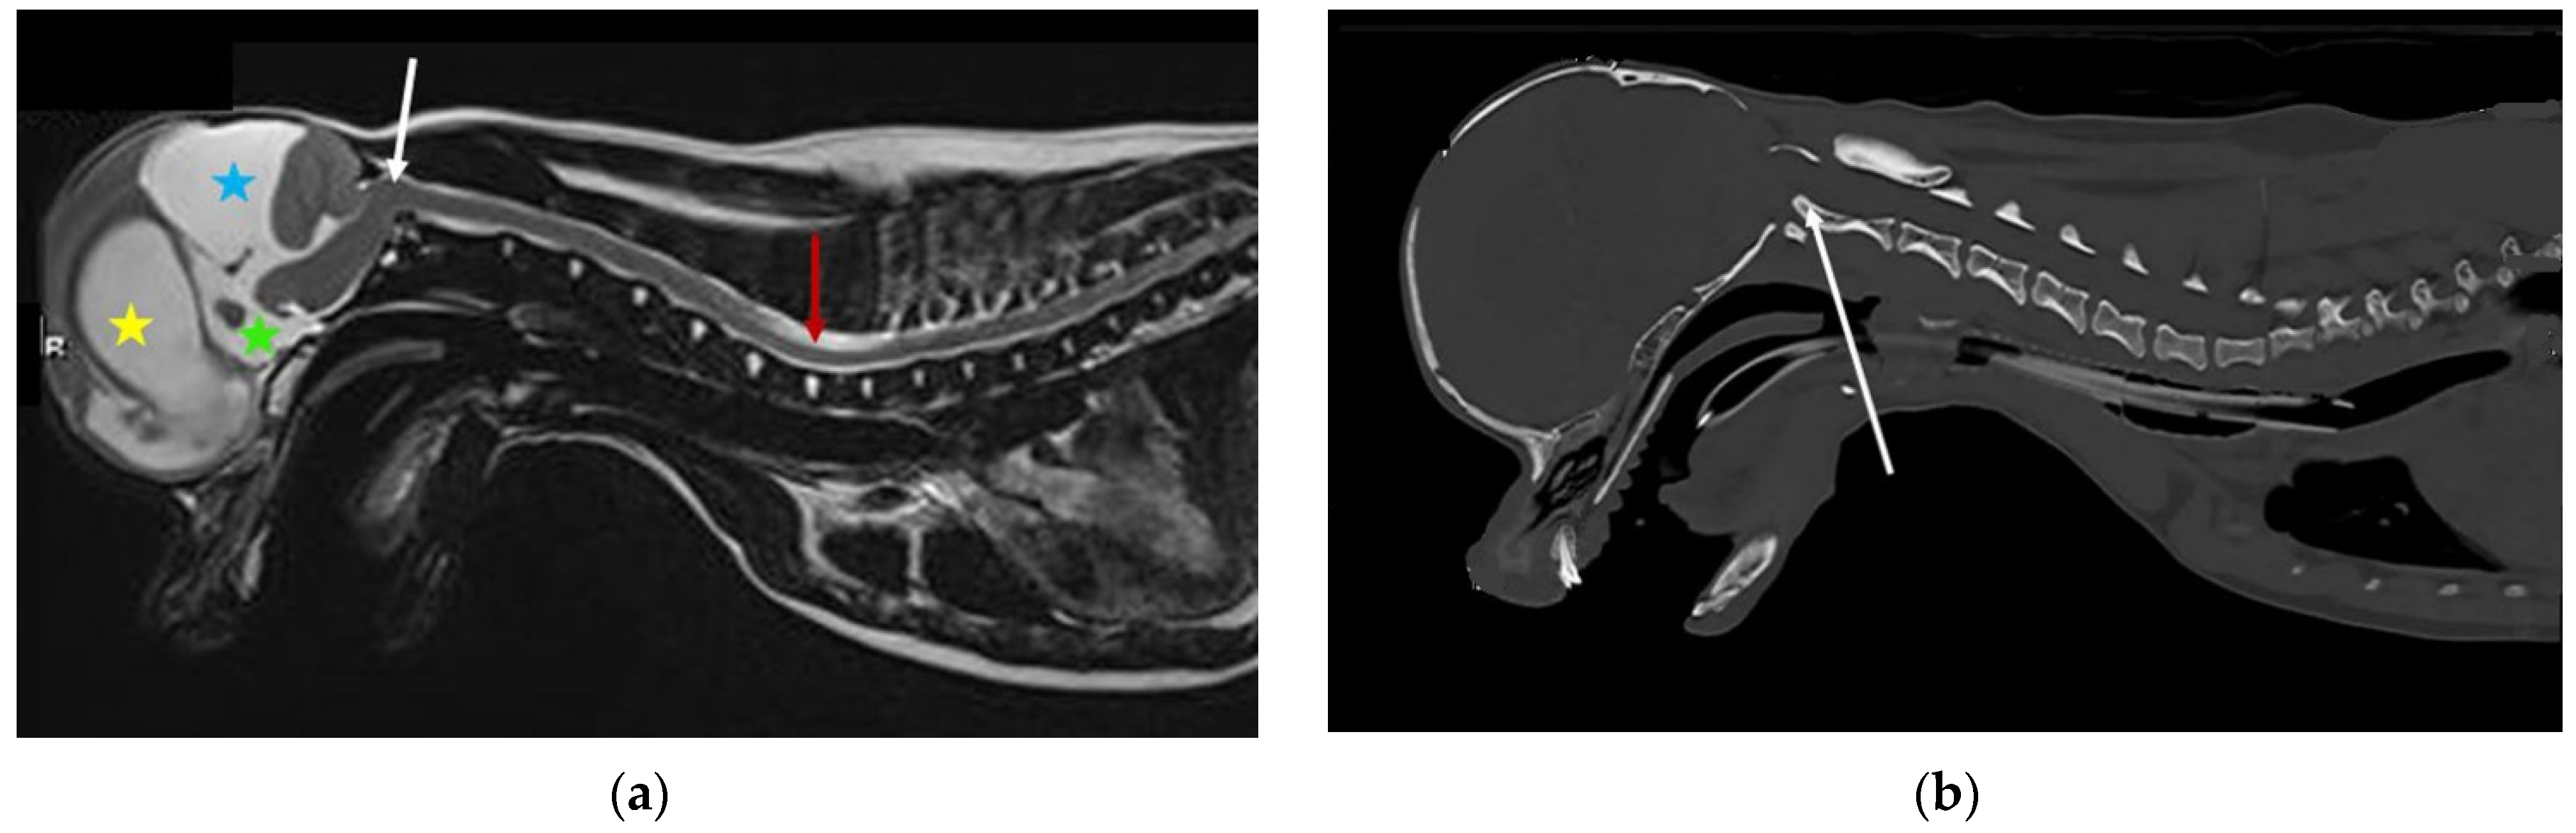

CSF passes from the ventricular to the subarachnoid space via the lateral apertures of the fourth ventricle (in humans, referred to as the foramen of Luschka). Primates have an additional foramen of Megendie in the median plane between the fourth ventricle and cisterna magnum [67]. In species other than primates, the fourth ventricle and cisterna magna are separated by the caudal medullary velum [67]. The authors hypothesize that a reduced caudal cranial fossa volume in some brachycephalic breeds results in obstruction of this CSF pathway, contributing to the tendency for ventriculomegaly and syringomyelia (Figure 2).

Figure 2.

Possible lateral aperture obstruction in a three-year-old Boston terrier with ventriculomegaly and early syringomyelia. (a) T2-weighted midsagittal brain. There is dilatation of the lateral (blue star), third (pink arrow), and fourth ventricle (blue arrow) with syringomyelia (green arrow). There is hyperdynamic flow of the CSF in the region of the obex, as evidenced by the hypointense fluid void sign (yellow arrow). The bulging caudal medullary velum can be appreciated (red arrow). There is marked reduction of the olfactory bulbs (white arrow), with ventral rotation of the brain because of brachycephaly, in addition to reduction of the nasal cavity. Consequently, reduced absorption of CSF through the olfactory lymphatics is suspected. (b) T2-weighted transverse brain at the level of the lateral aperture of the fourth ventricle (yellow arrows). The Boston Terrier in (a) is on the left and a normal brachycephalic dog on the right. The lateral apertures in the Boston Terrier cannot be appreciated. There is an absence of hyperintense CSF, and obstruction of these CSF pathways are suspected (images created by C. Rusbridge and S.P. Knowler).